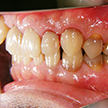

4. 初診時下顎

主訴である右下7番は早々に健康保険内インレー処置としました。下顎に関しては上顎のような問題は特になさそうです。しいて言えばテトラサイクリン等によると考えられる歯の変色でしょうか。